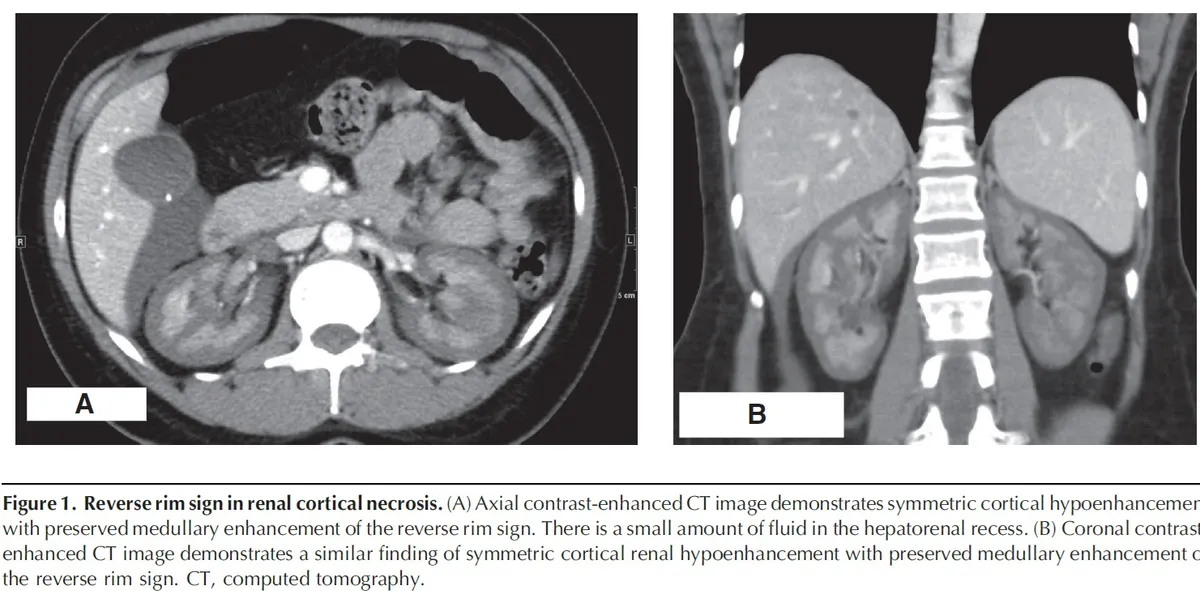

Nos dias seguintes, a creatinina sérica aumentou para 13 mg/dl, acompanhada de anúria. Realizado tomografia computadorizada de abdome (imagem da capa do post) que revelou sinais de necrose cortical renal (NCR), sinais de reversão renal (córtex hipodenso quando comparado a medula renal) com presença de um trombo na veia cava inferior e na veia gonadal direita. A paciente iniciou hemodiálise devido aos sintomas urêmicos e permaneceu dependente da diálise por cerca de dois meses. Após seis meses, a creatinina sérica caiu para 2,4 mg/dl, com um clearance de creatinina de 33 ml/min e proteinúria subnefrótica de 300 mg/d. A paciente continuo em tratamento conservador com diuréticos de alça em baixa dose e anticoagulação.

A NCR é uma forma grave e frequentemente irreversível de lesão renal isquêmica, resultante de uma redução prolongada da perfusão arterial renal. Esta condição é geralmente associada à CIVD e apresenta-se com início abrupto de oligúria ou anúria, algumas vezes acompanhada de hematúria macroscópica e dor no flanco. A TC com contraste mostrou a preservação da medula renal e a hipocaptação cortical (rim reverso), confirmando o diagnóstico de NCR.